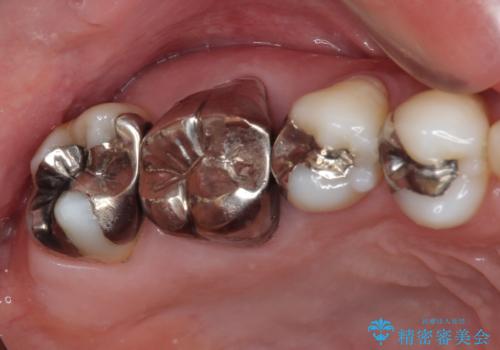

不快感が続く奥歯 外科処置を併用したセラミック補綴治療

奥歯が痛い セラミッククラウンでの虫歯治療